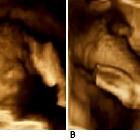

Antenatal ultrasound

Thus identification of a dividing membrane or two placentas excludes the diagnosis. Definitive sonographic features will depend on the type of fusion.

- non-separable skin contours with an inability to separate the fetal bodies

- both fetal heads persistently at the same level

- backward flexion of the cervical spine (due to the fact that most conjoined twins are fused ventrally and face each other

- constant relative fetal positions